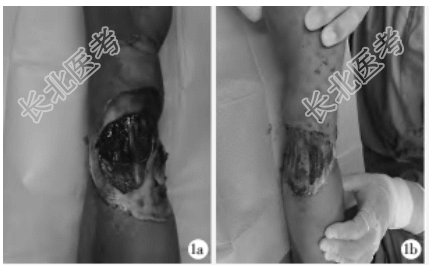

- [材料题] 患者,男,44岁,因“机器挤压左前臂后疼痛、功能障碍5h”入院。患者入院前5h干农活时左前臂被卷入机器皮带中,摩擦半小时后被救出,前臂疼痛、活动受限、手部无血运,辗转多家医院均被告知需要截肢,后来本院就诊。既往身体健康。查体:左前臂掌侧及背侧均有一皮肤热压伤创面(图1a,1b),皮肤呈皮革样改变,左手皮肤苍白,末梢温度、张力低,毛细血管反应消失,感觉减退,腕关节活动部分受限,屈指部分受限,指间关节伸直受限。X线片示:左前臂、左腕、左手未见骨折及脱位。入院诊断:左前臂挤压伤。